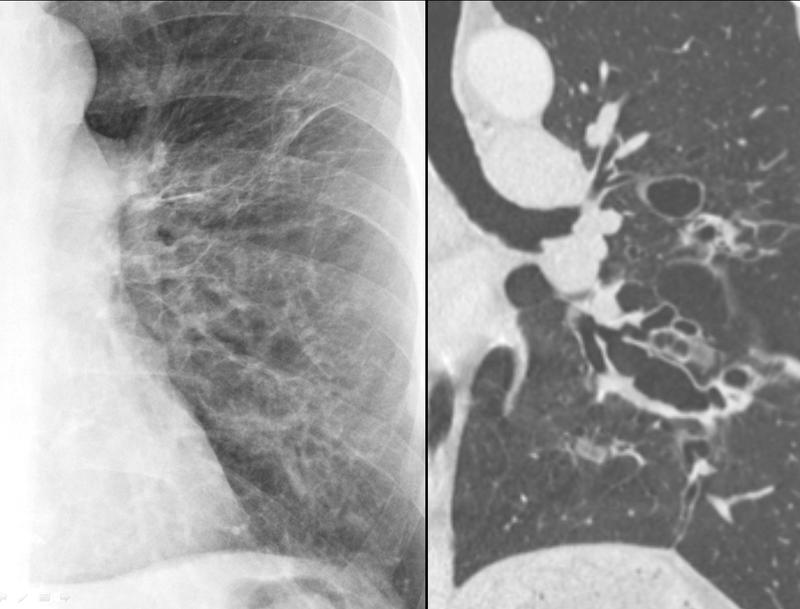

Bronchiectasis

Bronchiectasis with coronal CT